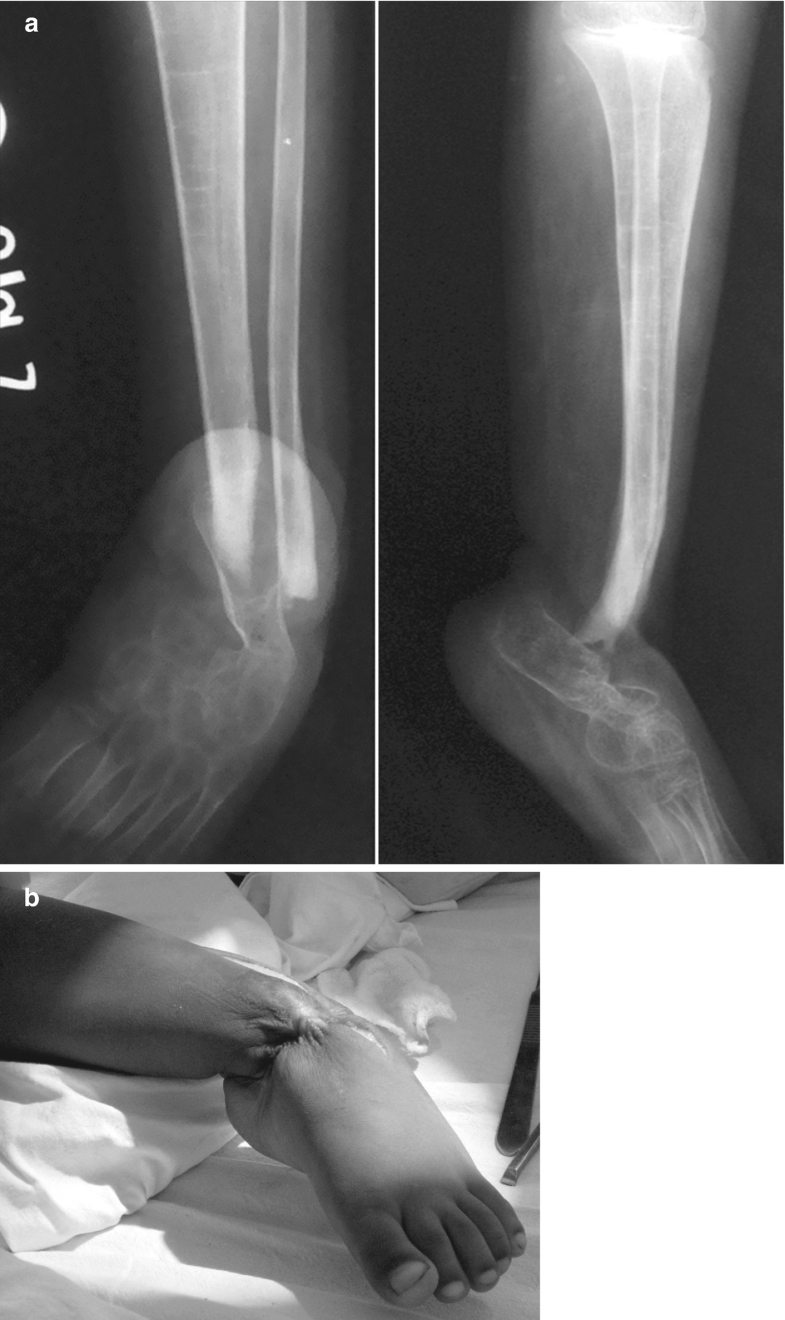

Neglected Septic Arthritis in Children SpringerLink Septic Foot Treatment Mild and some moderate infections. Diabetic foot infections require attention to local (foot) and systemic (metabolic) issues and coordinated management, preferably. Rarely, infection itself causes ulceration. If not treated promptly and appropriately, diabetic foot infections can become. How do you treat sepsis? Sepsis treatment needs to begin immediately. It can either be local or systemic. Diabetic foot infections (dfis) typically. Septic Foot Treatment.

Osteomyelitis and septic joint on xray in patient with history of Septic Foot Treatment If not treated promptly and appropriately, diabetic foot infections can become. Diabetic foot infections require attention to local (foot) and systemic (metabolic) issues and coordinated management, preferably. While all wounds are colonized with. Treatment requires early incision and. Antibiotic therapy should cover commonly isolated organisms and reflect local resistance patterns, patient preference, and the severity of the foot infection. Mild. Septic Foot Treatment.